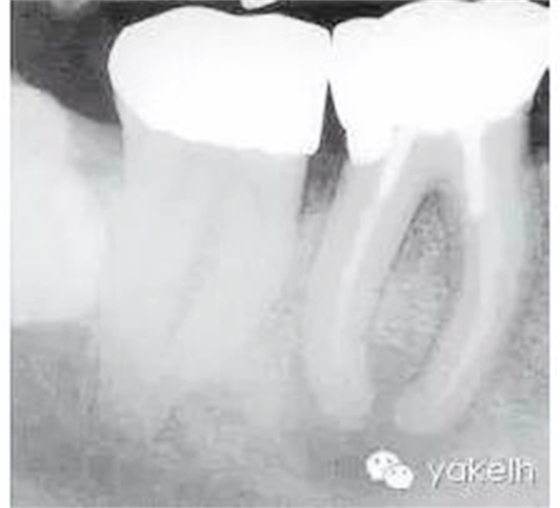

根尖X線片顯示什么(圖5.1.1)?

圖5.1.146術(shù)前X線片,顯示金屬冠修復(fù),每個牙根內(nèi)均有金屬樁,根管充填物均短于放射學(xué)根尖且有根尖周透射影。

金屬冠修復(fù)。

近遠(yuǎn)中牙根內(nèi)均有金屬樁。

在近中根內(nèi),樁的尖端向根管側(cè)壁偏移。

近遠(yuǎn)中牙根均有中度彎曲。

近遠(yuǎn)中根管充填物均短于放射學(xué)根尖。

近遠(yuǎn)中根尖周均有明顯的透射影。

右下頜第三磨牙(48)緊靠右下頜第二磨牙(47)遠(yuǎn)中。